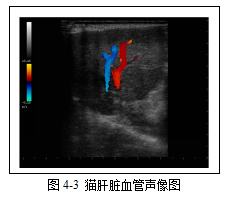

肝脏的血供由两套脉管构成,门静脉供应约80%的血液,肝动脉供应约20%的血液。肝脏血液的排流则是通过肝静脉进入后腔静脉来完成。B型超声成像时,仅肝静脉和门静脉能被显示,通常观察不到肝动脉。肝静脉和门静脉为无回声的、分支状的、平滑渐细的管状结构。通常肝静脉的管壁观察不到,而门静脉因为其管壁中含有更多的纤维成分,所以能够呈现产回声的管壁结构。当声束与肝静脉垂直时,肝静脉也可表现为较细的强回声管壁结构。在相同深度下,肝静脉和门静脉直径应相近。使用彩色多普勒超声可以对门静脉与肝静脉进行鉴别(图4-3)。使用标准的彩色标尺设定,门静脉因其血流为冲向探头而呈红色;肝静脉的血流为远离探头而呈蓝色。

肝脏的血供由两套脉管构成,门静脉供应约80%的血液,肝动脉供应约20%的血液。肝脏血液的排流则是通过肝静脉进入后腔静脉来完成。B型超声成像时,仅肝静脉和门静脉能被显示,通常观察不到肝动脉。肝静脉和门静脉为无回声的、分支状的、平滑渐细的管状结构。通常肝静脉的管壁观察不到,而门静脉因为其管壁中含有更多的纤维成分,所以能够呈现产回声的管壁结构。当声束与肝静脉垂直时,肝静脉也可表现为较细的强回声管壁结构。在相同深度下,肝静脉和门静脉直径应相近。使用彩色多普勒超声可以对门静脉与肝静脉进行鉴别(图4-3)。使用标准的彩色标尺设定,门静脉因其血流为冲向探头而呈红色;肝静脉的血流为远离探头而呈蓝色。